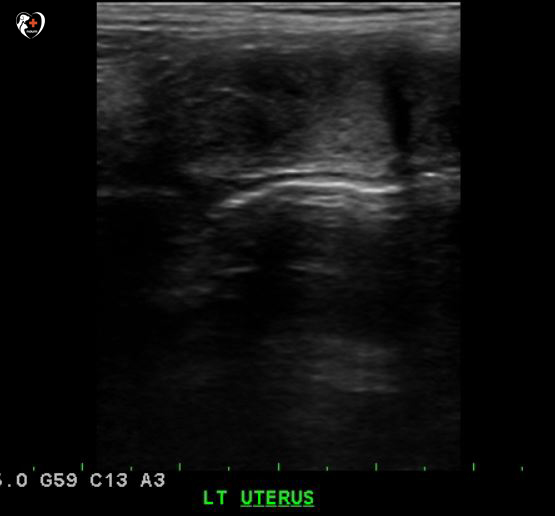

복부 초음파 검사를 실시하여 비뇨기계, 생식기계를 샅샅이 조사해 본 결과, 오른쪽 확장 자궁이 보였습니다.

오른쪽 사진을 보면 자궁이 크게 펼쳐져 있고 검은 부분이 잘려져 있군요?자궁축농증으로 인해 커진 것으로 확인되었습니다.